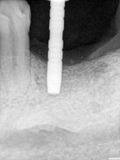

fredlibc | all galleries >> Galleries >> TZeng - 36 implant > R7.jpg

R7.jpg